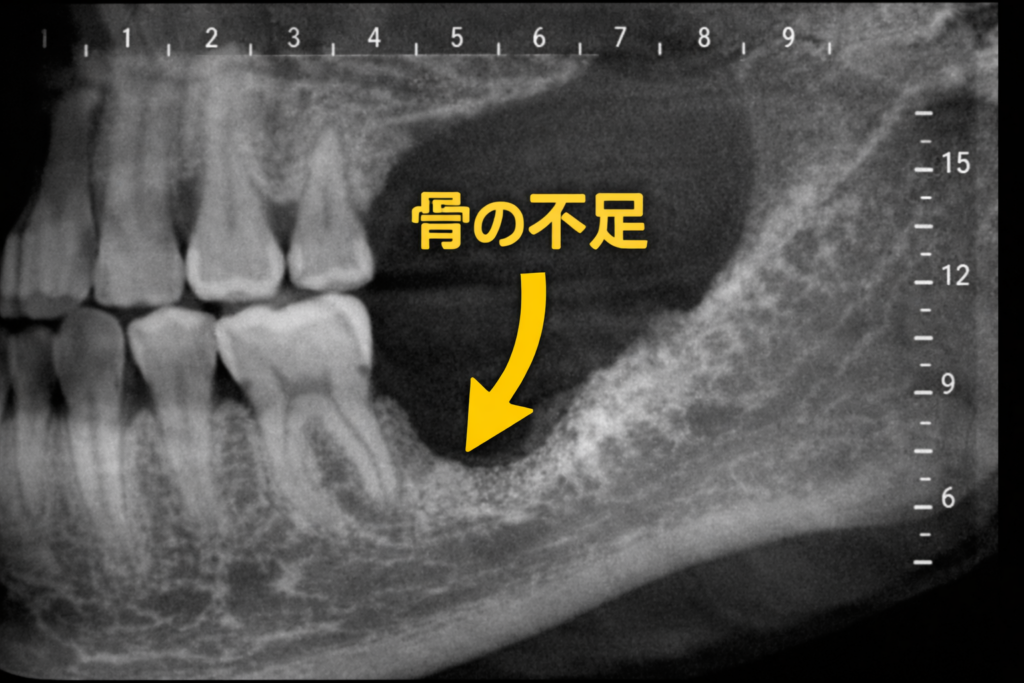

インプラント治療において、「骨の量」は成功を左右する非常に重要な要素です。しかし、歯周病や抜歯後の放置により、顎の骨が不足してしまうケースは少なくありません。そのような場合に活躍するのが「骨補填材」です。

骨補填材とは、骨が不足している部位に填入し、骨の再生を促すための材料です。単なるスペースの充填ではなく、新しい骨が形成されるための“足場”として機能します。

【写真①:骨が吸収している症例(術前CTまたは口腔内写真)】

※骨幅や高さが不足している様子

骨補填材にはいくつかの種類があります。例えば、自分の骨を使用する「自家骨」、人工的に作られた「人工骨」、ウシ由来などの「異種骨」などです。それぞれに特徴があり、症例に応じて使い分け、または組み合わせて使用します。

実際の治療では、「GBR(骨誘導再生法)」と呼ばれる方法がよく用いられます。これは、骨補填材を入れた後に特殊な膜(メンブレン)で覆うことで、歯肉の侵入を防ぎながら骨の再生を促す技術です。

骨補填材は時間とともに体内に取り込まれ、自分の骨へと置き換わっていきます。ただし、そのスピードや最終的な骨の質は使用する材料や患者さんの状態によって異なります。そのため、治療計画は非常に重要になります。

また、骨造成を行うことでインプラントの適応範囲が広がり、見た目や噛む機能の回復にも大きく貢献します。一方で、治療期間が延びる、感染リスクが伴うといった点も理解しておく必要があります。

骨補填材は、現代歯科における再生医療の中核を担う存在です。適切な材料選択と術式により、これまで難しかった症例でも治療が可能となっています。

インプラント治療を検討されている方で「骨が足りない」と言われた場合でも、骨補填材を用いた治療によって選択肢が広がる可能性があります。まずは精密な検査と診断を受け、ご自身に合った治療法を知ることが大切です。